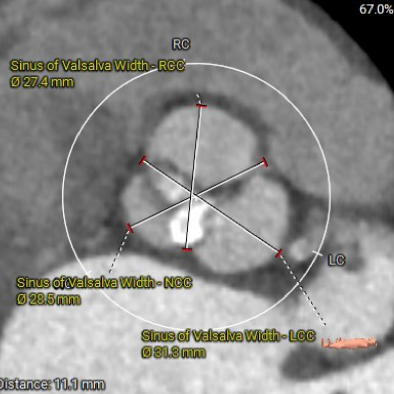

主动脉根部测量

瓣上结构测量

1. Type 1 型二叶式主动脉瓣,瓣叶增厚伴中度钙化,L-N间钙化融合嵴,左室流出道呈敞口型;

2. 冠脉开口高度尚可,左右冠瓣叶冗长,切线位左右冠瓣叶长度>>冠脉开口到瓣叶根部附着缘距离;冠脉未见明显钙化斑块;

3. 三窦大小不一,瓦氏窦、窦管交界内径偏小,升主动脉轻度扩张;左室腔内径尚可,心室壁未见明显增厚;